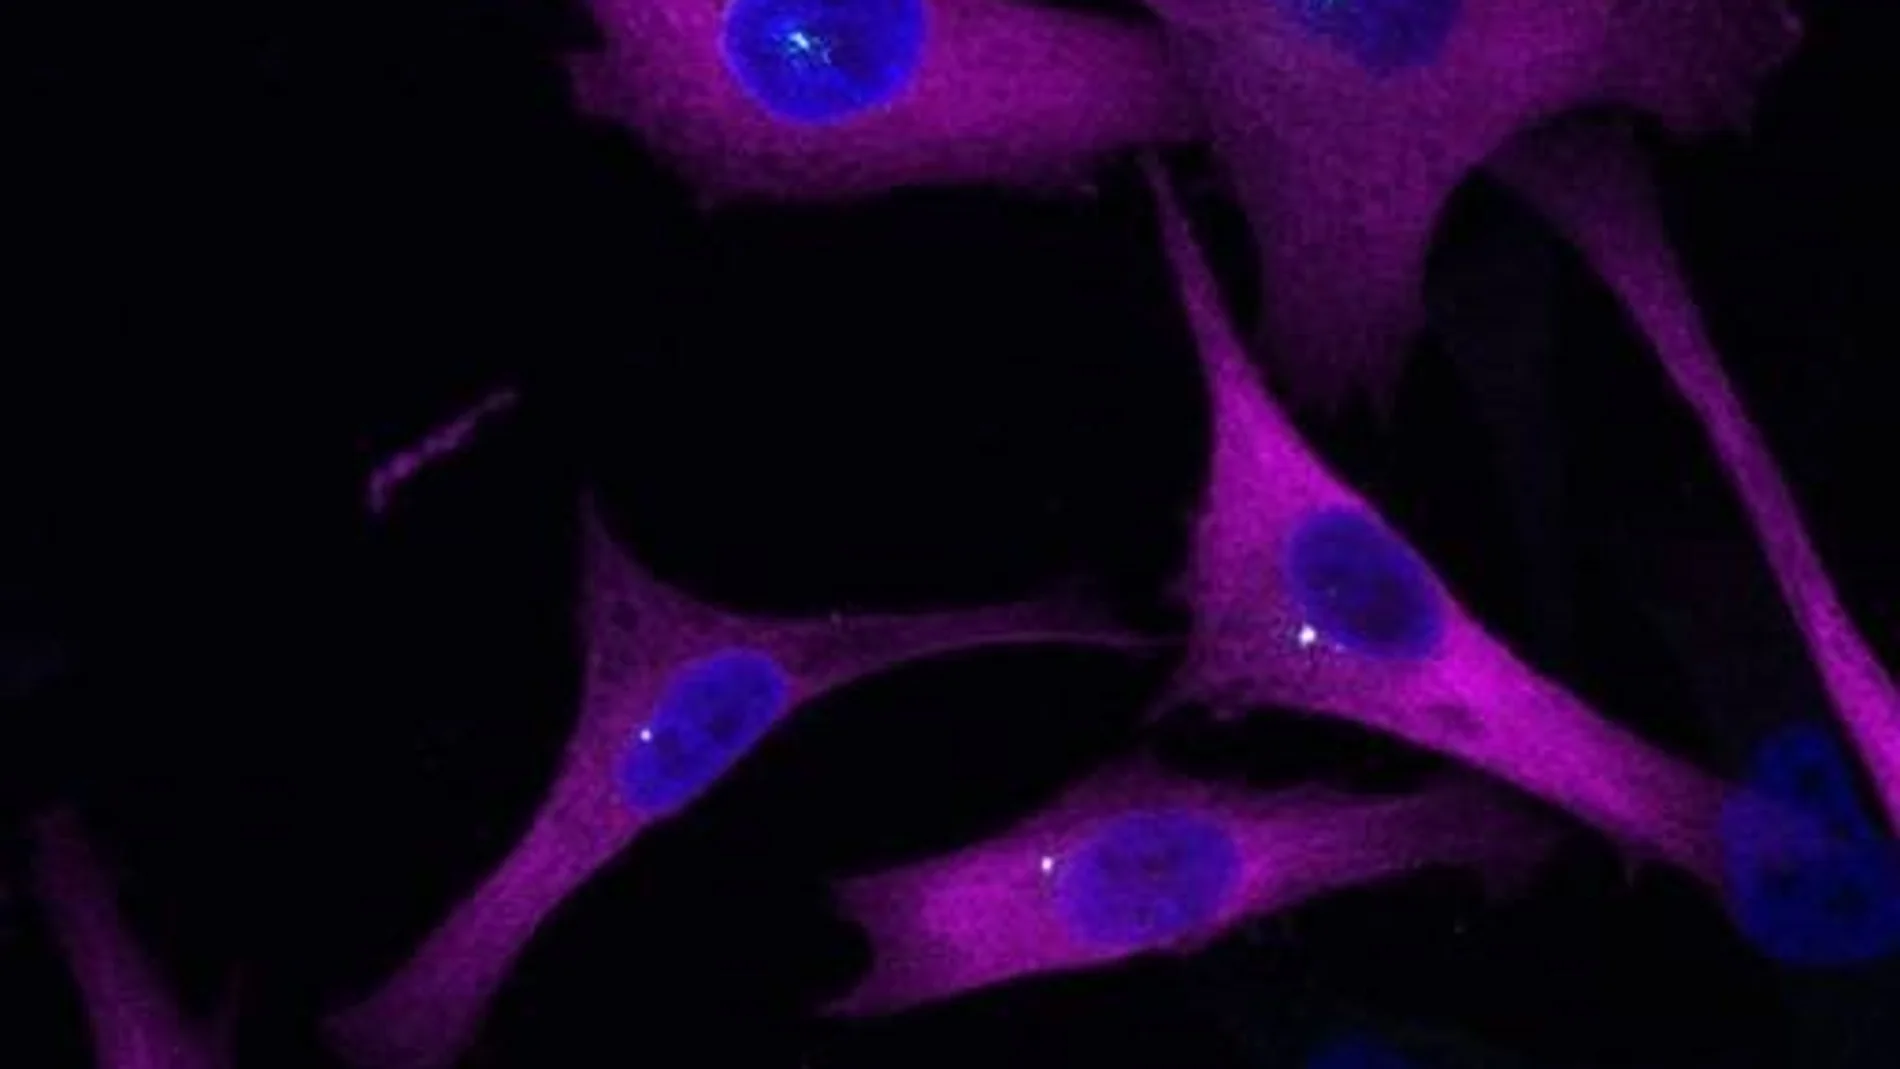

Trabajando con un par de líneas celulares de piel humana que diferían solo en su potencial metastásico, el equipo redujo los efectos de eIF2A. En las células cancerosas, las esferas tumorales tridimensionales dejaron de crecer y la migración en la placa de cultivo se ralentizó drásticamente. Sin embargo, la fabricación de proteínas apenas se vio afectada.

El equipo extrajo eIF2A de la célula utilizando un hilo de pescar molecular y catalogaron a qué proteínas asociadas estaba unida. Muchas resultaron ser componentes del centrosoma, una estructura molecular que organiza los microtúbulos y orienta a las células durante el movimiento. Cuando eIF2A estaba ausente, el centrosoma a menudo apuntaba en la dirección equivocada mientras las células intentaban avanzar.

Experimentos posteriores revelaron que eIF2A trabaja para preservar partes del centrosoma para que guíe a la célula en la dirección correcta durante el movimiento. La cola de la proteína es fundamental para la fuerza de migración de la célula. Al recortarle cola, la capacidad de movimiento de la célula quedó afectada, y esto podría dar lugar a una potencial diana terapéutica.

"La cola se comporta como un andamiaje, manteniendo partes clave de la brújula celular del melanoma en su lugar para que las células malignas puedan recorrer su camino fuera del tumor primario", dice Jennifer Jungfleisch, primera autora del estudio.